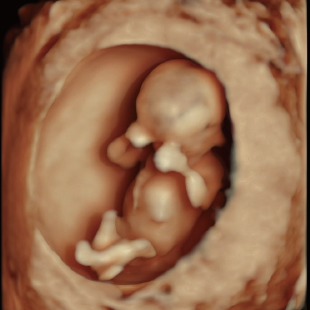

妊娠初期は、胎児がヒトとしての基本的な形をつくる大切な時期です。主に心臓、脳、消化器、四肢などの重要な臓器が作られますが、その大きさはとても小さいです。

初期スクリーニングでは、首の後ろのむくみ(Nuchal translucency: NT)や鼻の骨、心臓まわりの血流などを確認し、胎児の体の特徴や発育の様子を丁寧に観察します。 これらの所見は、染色体数の変化と関連することがある特徴として知られており、21トリソミー/18トリソミー/13トリソミーなどの染色体変化の可能性を評価する指標となります。(本検査のみで確定診断はできません) また観察可能な範囲において脳や脊椎、心臓、消化管、手足などに大きな形態の変化がないかについても確認を行います。

胎児ドックの様子_初期 胎児ドックの様子_初期 胎児ドックの様子_初期 胎児ドックの様子_初期 胎児ドックの様子_初期 胎児ドックの様子_初期 胎児ドックの様子_初期 胎児ドックの様子_初期